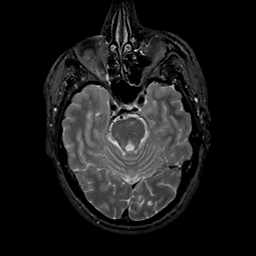

MR Study #11, May 5, 1991 -- Slice #16